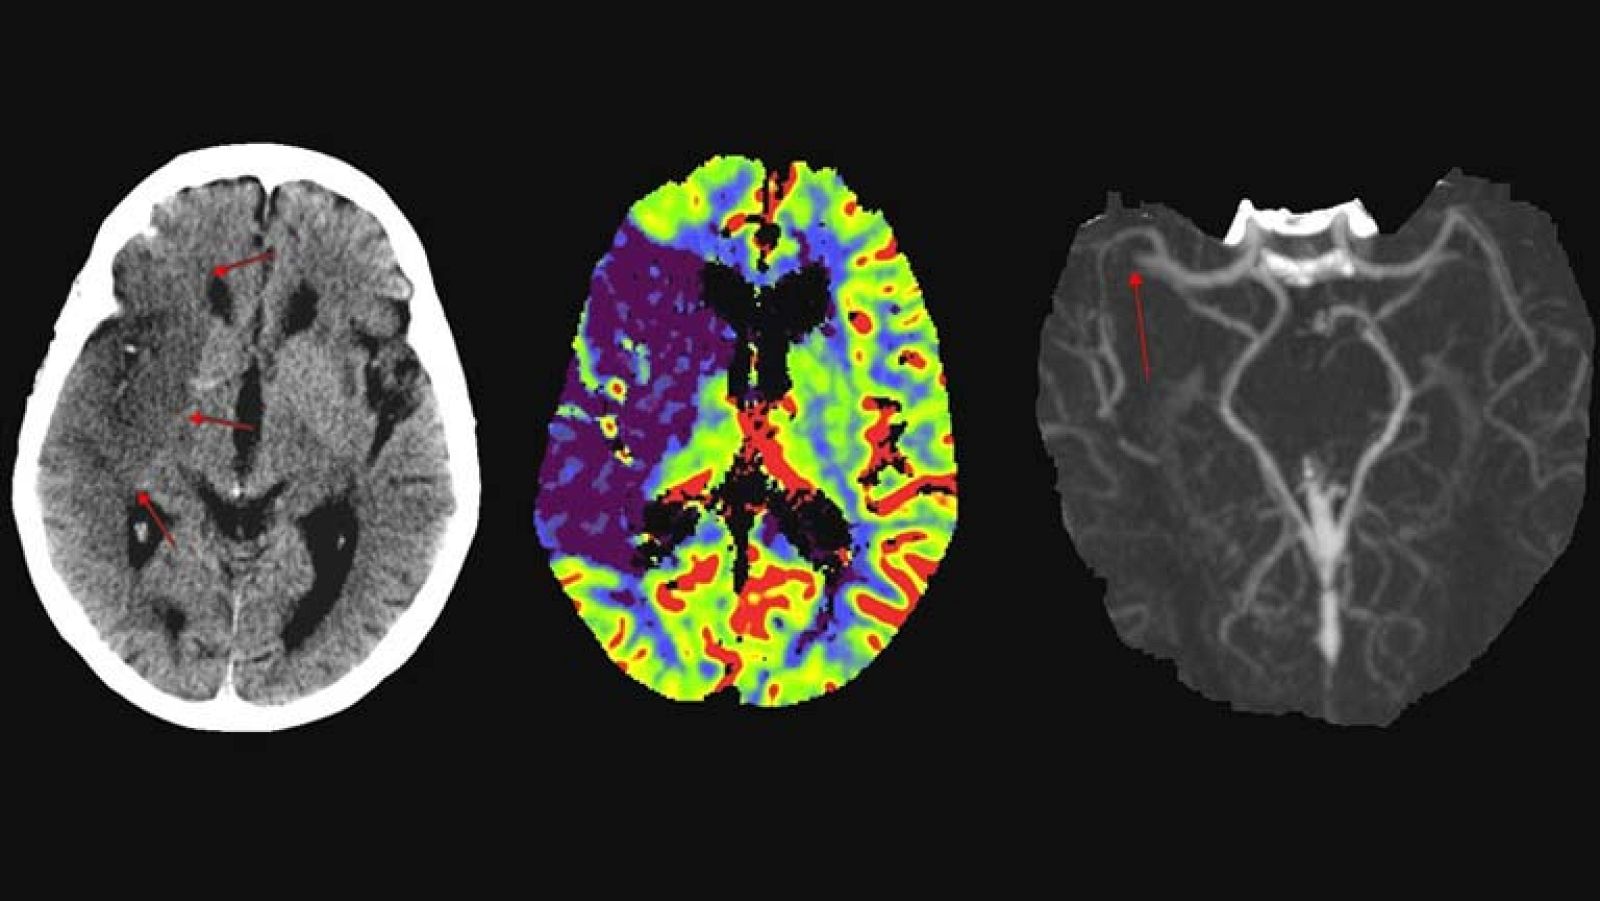

Imágenes de las consecuencias sobre el cerebro de distintos accidentes cerebrovasculares tomadas con Resonancia Magnética.

La isquemia cerebral es la tercera causa de muerte y la primera causa de discapacidad en los países industrializados. Se produce como consecuencia de la disminución transitoria o permanente del flujo sanguíneo cerebral y causa daño neuronal irreversible que provoca alteraciones neurológicas, según ha informado la UPV en un comunicado.

Una parte importante de este deterioro se debe a la alteración en los niveles de glutamato, el neurotransmisor excitador más abundante del cerebro que actúa a su vez como una potente neurotoxina cuando su concentración se eleva, como ocurre durante la isquemia.

El nuevo hallazgo pone de manifiesto que la molécula xCT, el intercambiador cistina-glutámico, se acumula hasta niveles letales para las neuronas durante la isquemia.

A su vez, los investigadores del CIC biomaGUNE, mediante técnicas de imagen cerebral funcional como el PET (del inglés, Tomografía por emisión de positrones) han observado que los niveles de xCT están elevados en ratas sometidas a isquemia, lo cual subraya su importancia en el proceso de ictus.